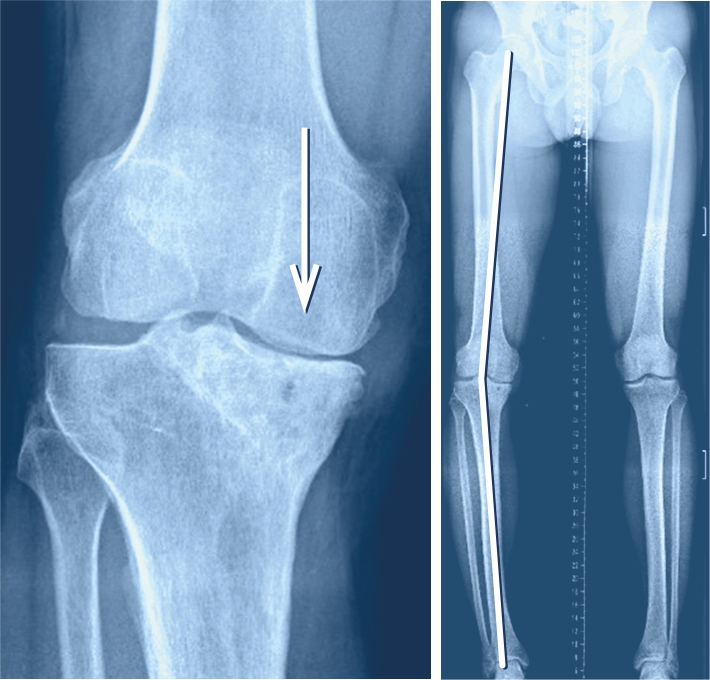

Im Verlauf des Lebens kommt es zu natürlichen Veränderungen der Beinachse. Säuglinge werden mit O-Beinen geboren. Nach dem Kleinkindalter verändert sich die Beinachse zu einem leichten X-Bein. Mit der Pubertät stellt sich dann meist eine gerade Beinachse ein. Dies ist der Fall, wenn sich im geraden Stand bei geschlossenen Beinen Knöchel und Knie an der Innenseite berühren. Bleibt bei sich berührenden Knöcheln zwischen den Knien ein Abstand, spricht man von O-Beinen. Bleibt hingegen eine Lücke zwischen den Knöcheln, während die Knie sich berühren, spricht man von X-Beinen. Beim O-Bein verläuft die gewichttragende Achse durch die innen gelegene Fläche des Kniegelenks, beim X-Bein durch die aussen gelegene.

Für die Kniegelenkarthrose typisch sind belastungsabhängige Knieschmerzen im geschädigten Gelenkbereich, insbesondere bei den ersten Schritten (sogenannter Anlaufschmerz). Eine längere Belastung kann die Beschwerden noch verstärken. Die Varusgonarthrose (O-Bein) schmerzt tendenziell auf der Innenseite des Knies und die Valgusgonarthrose (X-Bein) auf der Aussenseite. Konventionelle Röntgenbilder bestätigen die entsprechende Diagnose.

Wenn nur auf der Innen- oder der Aussenseite des Kniegelenks eine Arthrose vorliegt, kann mit einer sogenannten Umstellungsosteotomie oft eine Linderung der Beschwerden über Jahre erzielt werden, ohne dass ein künstliches Gelenk eingebaut werden muss. Wenn nur die Innenseite des Kniegelenks von der Arthrose betroffen ist (O-Beine), während die äussere Gelenkhälfte völlig schmerzfrei ist, kann mittels Umstellungsosteotomie durch eine Knochendurchtrennung im oberen Schienbeinbereich ein leichtes X-Bein erzielt werden (sogenannte Valgisationsosteotomie), was zur Entlastung der inneren Gelenkhälfte führt. Ziel ist es, unter Erhalt des eigenen Gelenks die Schmerzen zu vermindern und das Fortschreiten der Arthrose aufzuhalten oder zumindest zu verzögern. Zur Behandlung der Valgusgonarthrose (X-Fehlstellung) erfolgen Knochendurchtrennung und Achsenkorrektur knienah meistens am Oberschenkel (Varisationsosteotomie). Ist die Fehlstellung sehr ausgeprägt ist es manchmal sogar notwendig, in derselben Operation am Ober- und Unterschenkel einen Korrektureingriff vorzunehmen.